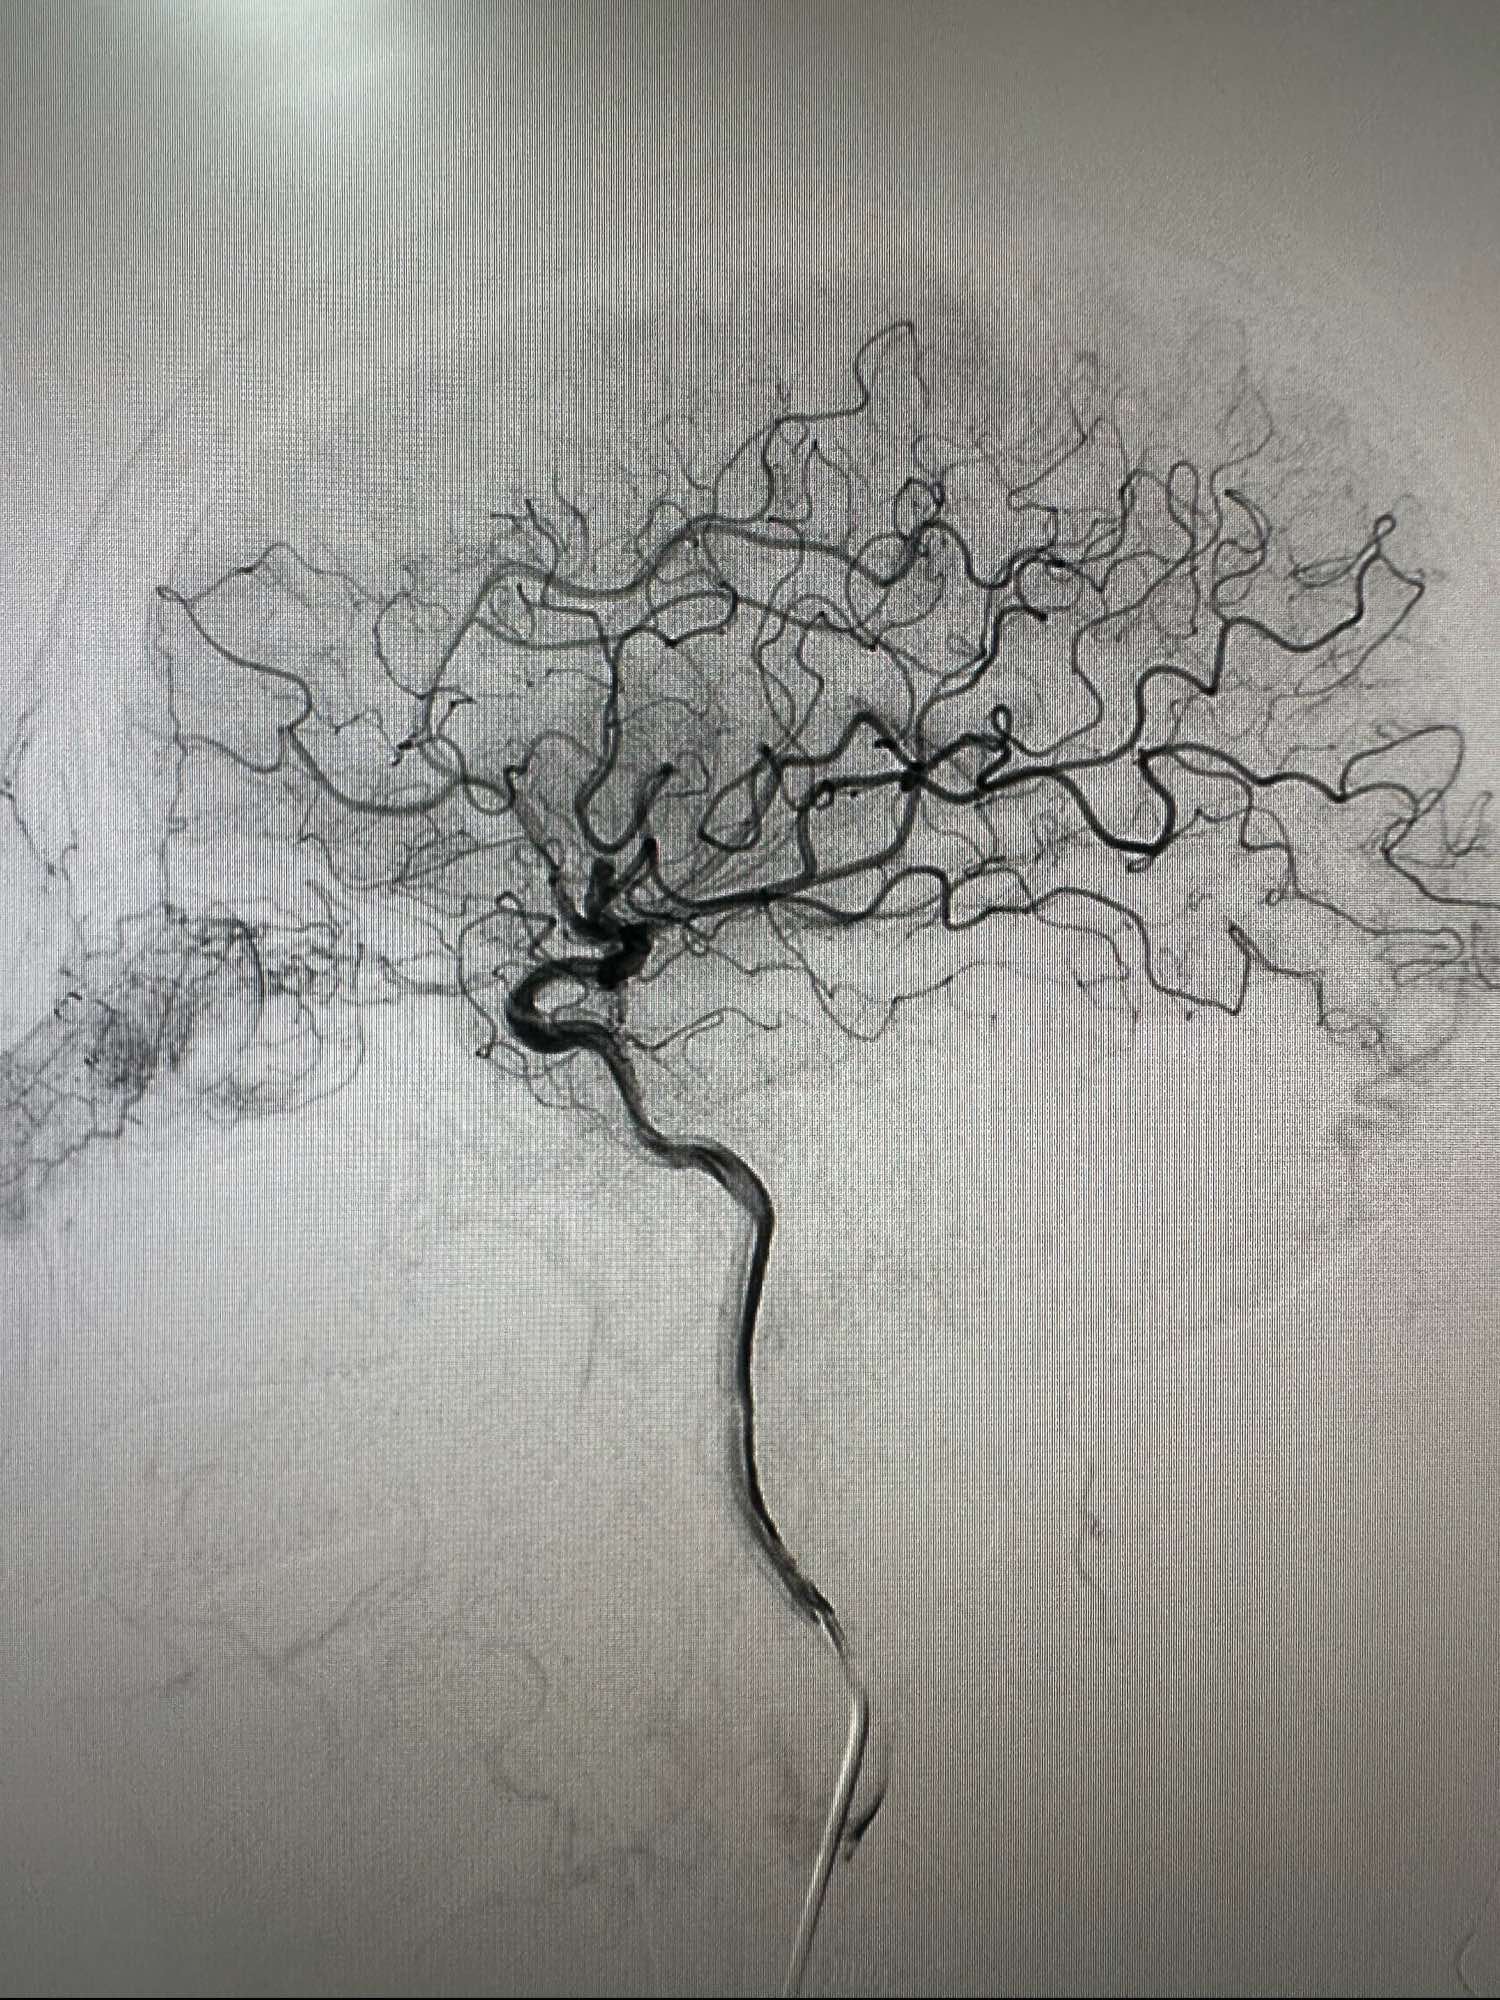

左侧颈内动脉造影正位

侧位